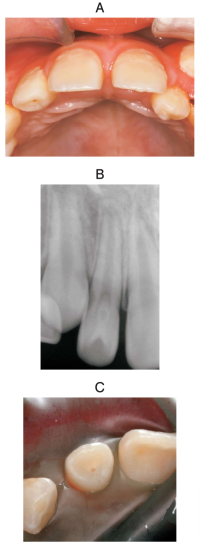

10 歳の女児。上顎右側側切歯の凹みが気になり来院した。自発痛と冷温痛はみられない。歯髄電気診で正常反応を示した。検査の結果、ある処置を行うこととした。初診時の口腔内写真、エックス線画像及びラバーダム装着時の口腔内写真を別に示す。

適切な処置はどれか。1つ選べ。